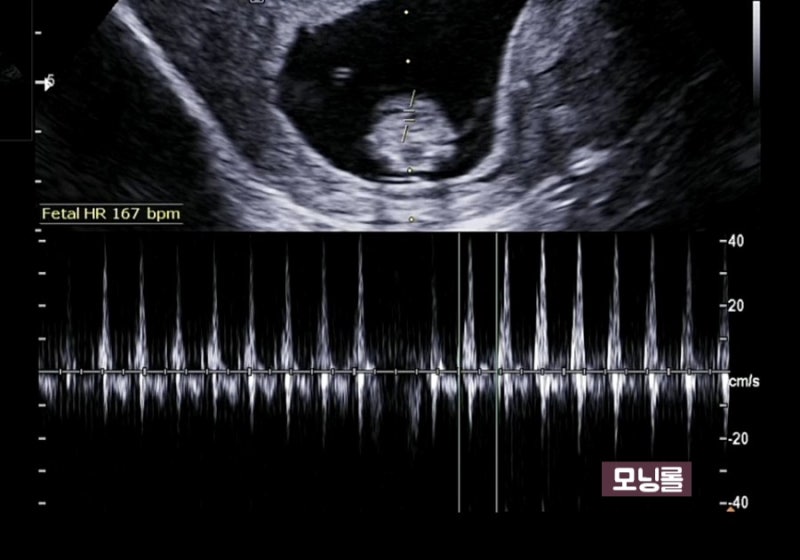

1.1차 정밀초음파&통합선별검사 임신 12주차는 중요한 시기로 아이가 많이 커져 배 초음파가 가능해져 1차 정밀초음파검사와 통합선별검사를 하게 됩니다.

정밀초음파는 1차(10~13주), 2차(20~21주)에 시행되는데, 1차 정밀초음파 검사: 태아목 투명대(NT) 두께 측정으로 태아의 염색체, 심장에 이상이 있는지 확인합니다.보통 2.5mm 미만이 정상입니다(목투명대란 아기를 둘러싼 차양막에서 목까지의 빈 부분입니다.)